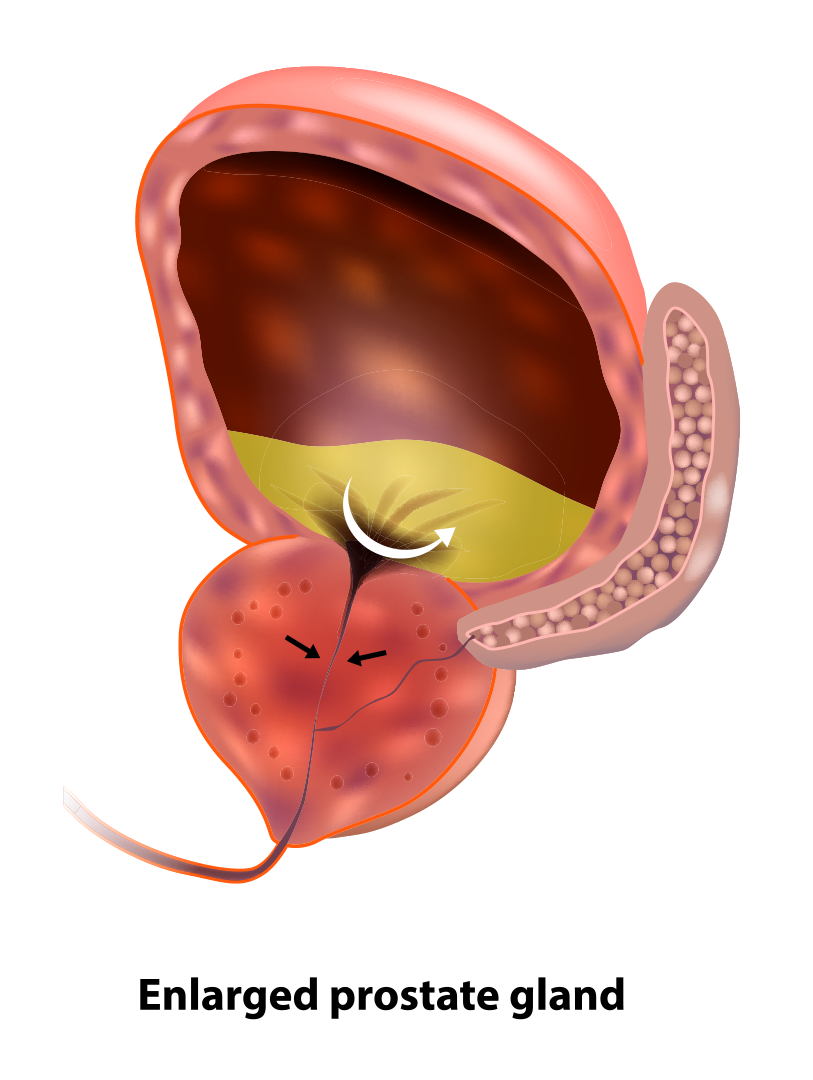

Diagnostic tests benign prostatic hyperplasia (bph) several tests help to confirm benign prostatic hyperplasia (bph) diagnosis:

Diagnostic tests benign prostatic hyperplasia (bph) several tests help to confirm benign prostatic hyperplasia (bph) diagnosis:

Diagnostic tests benign prostatic hyperplasia (bph) several tests help to confirm benign prostatic hyperplasia (bph) diagnosis:

Diagnostic tests benign prostatic hyperplasia (bph) several tests help to confirm benign prostatic hyperplasia (bph) diagnosis:

Diagnostic tests benign prostatic hyperplasia (bph) several tests help to confirm benign prostatic hyperplasia (bph) diagnosis:

Diagnostic tests benign prostatic hyperplasia (bph) several tests help to confirm benign prostatic hyperplasia (bph) diagnosis:

Diagnostic tests benign prostatic hyperplasia (bph) several tests help to confirm benign prostatic hyperplasia (bph) diagnosis:

Diagnostic tests benign prostatic hyperplasia (bph) several tests help to confirm benign prostatic hyperplasia (bph) diagnosis:

Diagnostic tests benign prostatic hyperplasia (bph) several tests help to confirm benign prostatic hyperplasia (bph) diagnosis:

Diagnostic tests benign prostatic hyperplasia (bph) several tests help to confirm benign prostatic hyperplasia (bph) diagnosis:

Diagnostic tests benign prostatic hyperplasia (bph) several tests help to confirm benign prostatic hyperplasia (bph) diagnosis: